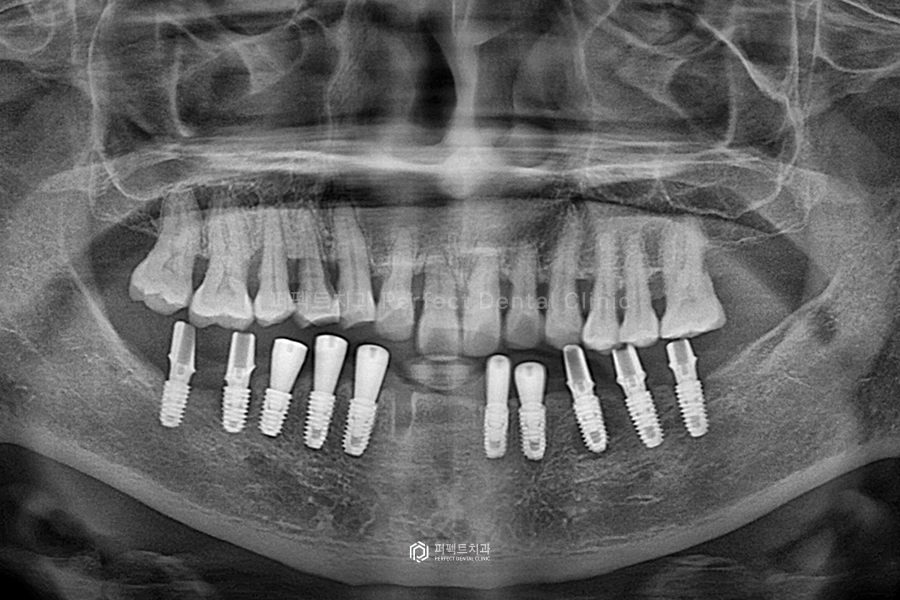

윗니는 아까 말씀드린 대로 상태가 좋지는 않지만 꼭 발치해야 하는 치아만 발치를 하고, 살릴 수 있는 치아는 신경치료를 해서 시간이 걸리더라도 최대한 오래 사용할 수 있도록 계획하였습니다.

윗니까지 최종 치료를 마무리 한 사진입니다. 이렇게 하얗게 끝까지 잘 들어가 있는 것은 신경치료가 잘 됐다는 것을 의미합니다.

윗니 같은 경우에는 왼쪽 어금니 하나가 없는데 아래쪽에도 치아가 없어서, 즉 맞닿는 치아가 없어서 이렇게 마무리 하기로 하였습니다.